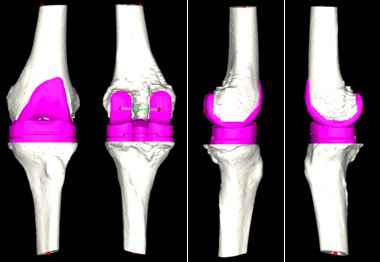

对此,张弛团队在与患者及家属充分沟通后,决定使用人工智能系统辅助置换全膝关节。专家在系统中上传患者的CT资料,人工智能便快速完成了术前规划,其模拟的假体型号及角度、位置十分精准。

人工智能术前规划模拟出精准的假体大小和位置。

“传统的全膝关节置换术极其依赖术中所见及骨科医生的临床经验,医生常需于术中反复比对以寻找最适假体大小,由于患者个体差异大、病情复杂等问题,导致全膝关节置换术后患者满意度偏低。”张弛解释说,“该患者病情复杂,通过人工智能辅助,能够在术前精准规划,帮助手术更快速、更精准的实现。”

术中运用后交叉韧带保留型的假体进行膝关节表面置换,术后复查照片精准复制了人工智能测量的结果。